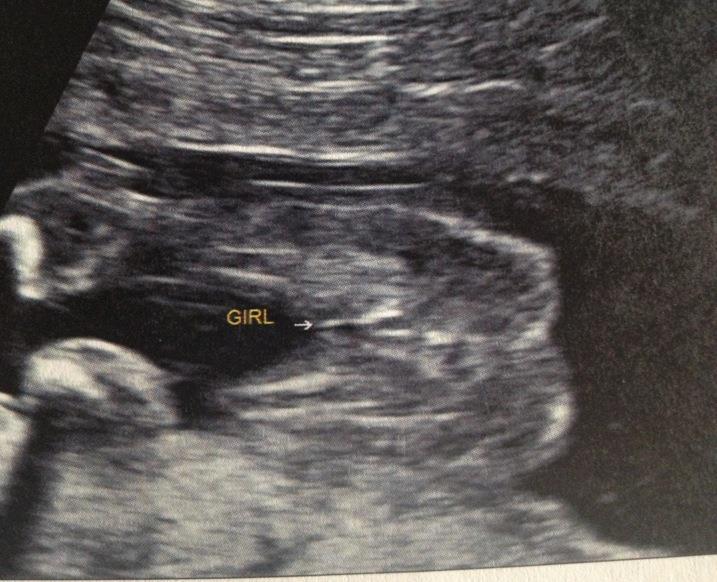

ITS A GIRL ISNT IT?

Attachment 7784

Yes it is :)

YUP that's a GIRL!